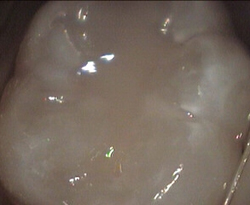

Unusual prevalent but superficial groove pattern on permenant molar after Sealed

unusual wide but superficial decay after